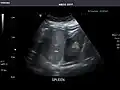

Abdominal Ultrasound (Full Exam)

STRUCTURED REPORT

(Technique: Transabdominal ultrasonography; Device: Toshiba Aplio XG)

Spleen: Normal in size.

Spleen -